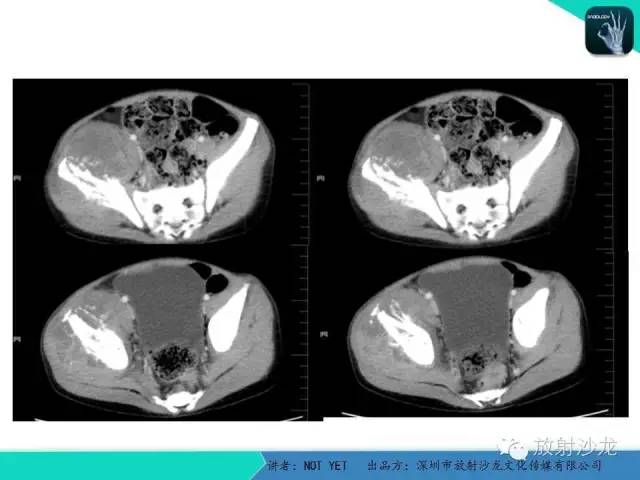

【病例】右侧髂骨Ewing肉瘤1例CT影像表现